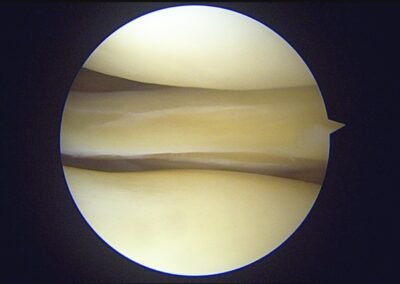

GalleryShoulder rotator cuff repair Meniscus root repair Meniscus repair Bankart repair for recurrent shoulder dislocation ACL reconstruction Machines Instruments